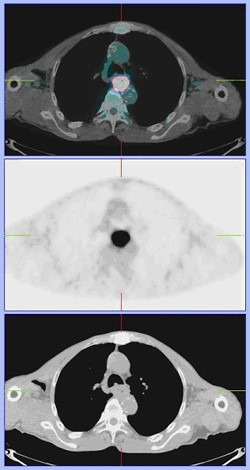

식도암에서 PET 스캔 (PET/CT)

양전자방출단층촬영(PET)은 현재까지 나와 있는 암 검사법 중에 가장 민감하다고 알려져 있습니다. 기존의 검사법에서 밝혀지지 않은 원격 전이의 진단이나 림프절 전이 여부의 판정에 유용합니다.

양전자방출단층촬영(PET/CT)검사는 양전자방출단층촬영(PET)이라는 검사와 전산화단층촬영(CT)을 기계적으로 결합한 검사로서 기존의 양전자방출단층촬영(PET)이나 전산화단층촬영(CT)보다는 진단률이 높으며 암이 전이된 부위의 해부학적 위치를 정확하게 판단할 수 있습니다.